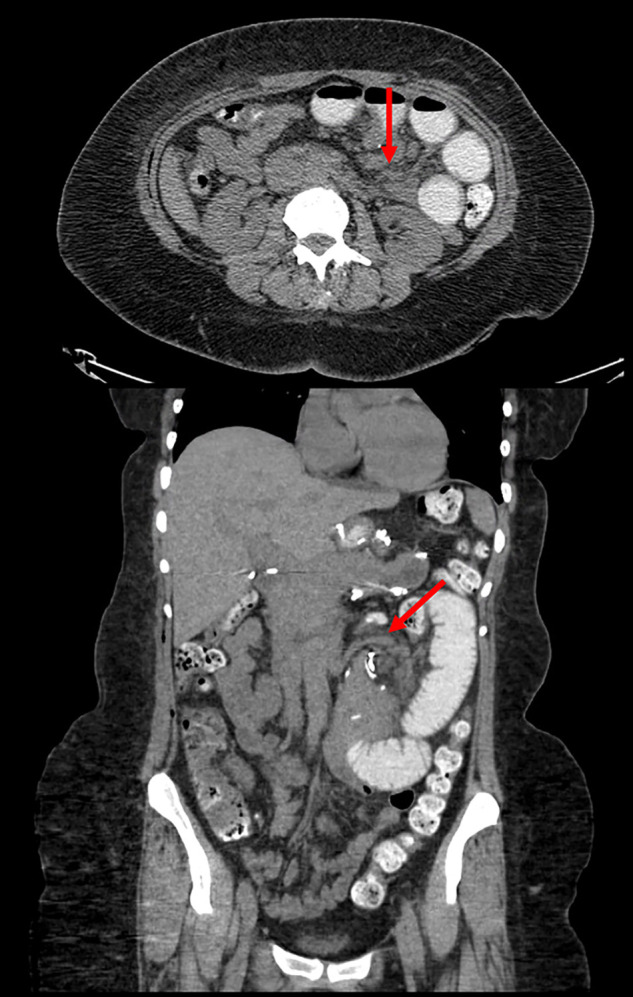

Case description: We describe the case of a 52-year-old female with a history of LRYGBP who presented with abdominal pain and emesis due to an internal hernia at Peterson's defect, requiring subsequent laparoscopic repair. On postoperative day three, the patient presented again with recurrent abdominal pain and emesis. Repeat exploratory laparoscopy found a separate internal hernia involving the jejunojejunal window with the previously repaired Petersen's defect intact.

Discussion: This case illustrates a unique scenario of a patient post-LRYGBP with multiple internal hernias at the Peterson's space and the less common jejunojejunal window, which was missed during the index surgery. Failure to identify simultaneous hernias may result in additional invasive intervention and further morbidity.